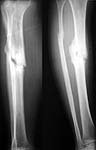

A male 26 y.o. sustained closed tibial shaft fracture after a car accident (pedestrian injury) Feb 7, 2002. In a small local hospital the Ilizarov fixator was applied, reduction was poor. 3 months later it was removed and replaced by plaster cast. The patient reported after ex-fix removal mobility at the site, no wire tract infection. A month later he himself decided to take off the cast. Now walks with cane and limp, marks pain over the site. No obvious mobility found at examination. Recent films (AP and 3/4) attached.

What diagnosis is correct to date? Pseudarthrosis? Delayed union? Something else?